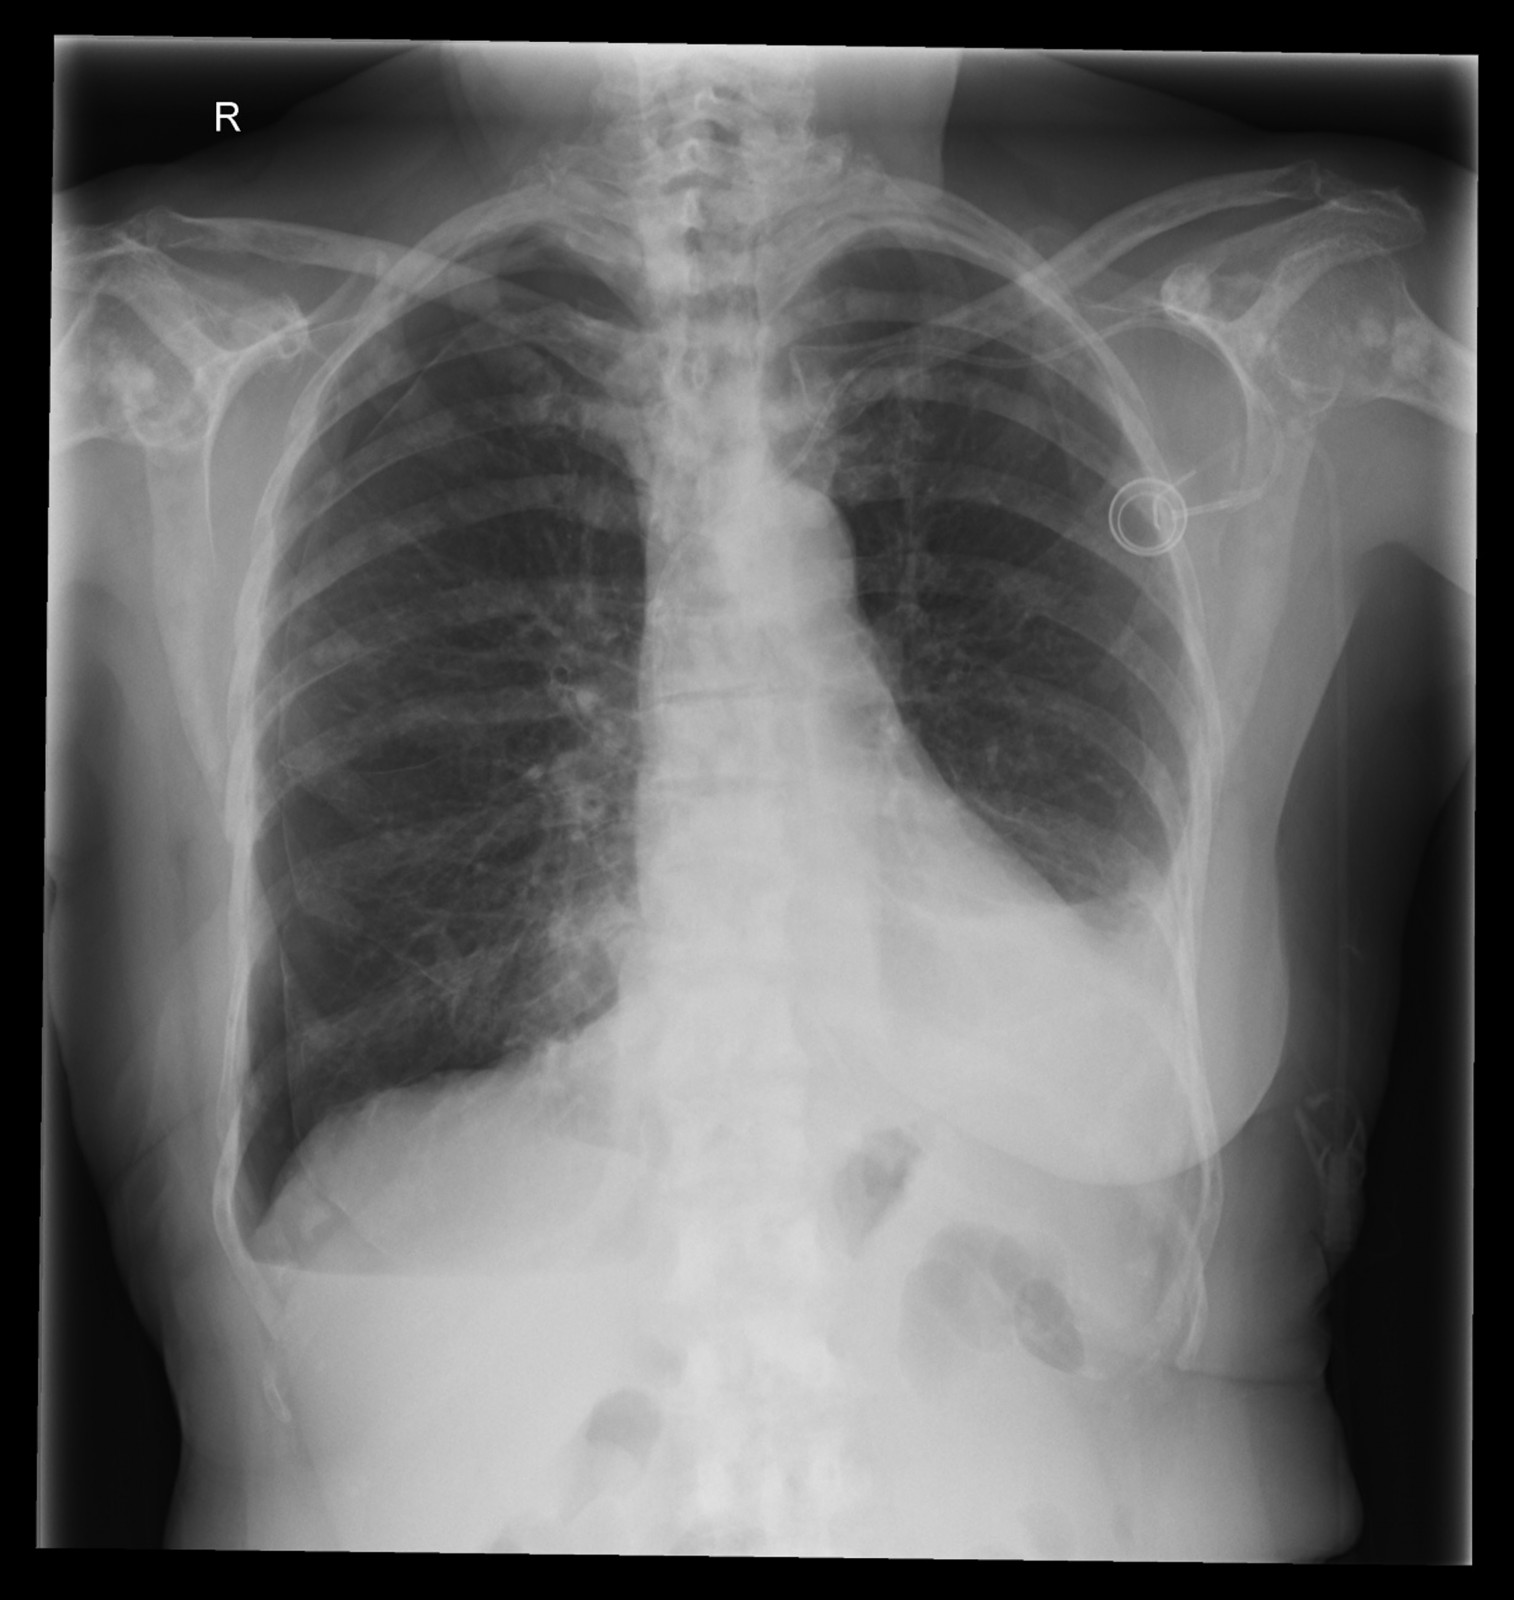

Röntgenfall des Monats Mai 2017 mit Auflösung

74 jährige Patientin mit diffusen Skelettschmerzen und akut aufgetretener Dyspnoe. Z.n. Mammakarzinom rechts.

ap

seitlich